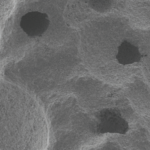

Go beyond the limits of Collagen Membrane

Any location, Any Size & Any Situation for GBR, i-Gen ensures regenerating minimum 2.5mm buccal bone. The regenerating of more than 2.5mm of buccal bone to minimize bone loss after GBR and maximize the life of implant.